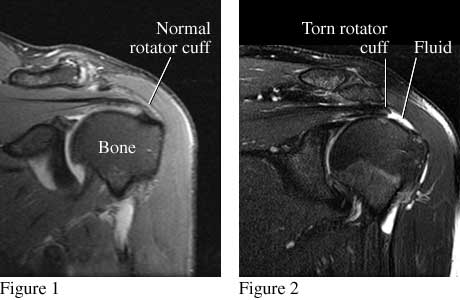

Rotator Cuff MRI